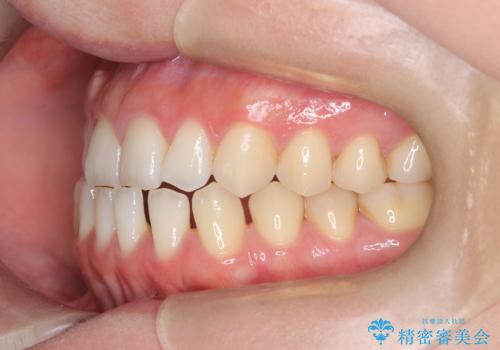

すきっ歯・切端咬合・空隙歯列|インビザラインで11ヵ月で治療完了

- すきっ歯と切端咬合(上下の前歯が先端で当たるかみ合わせ)を主訴にご来院された患者様です。

矯正検査を行った結果、非抜歯でインビザラインによる治療が可能と判断し、マウスピース矯正で改善を行いました。

11ヵ月で矯正治療が終了し、前歯の隙間も改善、見た目とかみ合わせも良好な状態となり、患者様にも大変ご満足いただけました。